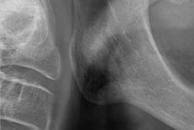

Exploración extraoral

Se constata reducción del tercio facial inferior produciendo a nivel estético una apariencia envejecida por formación de surcos en las comisuras labiales («líneas de marioneta») secundarias a una disminución de la dimensión vertical por desgaste dental (Figuras 5 y 6).

Exploración radiológica

Mediante CBCT constatamos atrofias óseas severas y disminución de soporte óseo periodontal en relación con las piezas dentales.